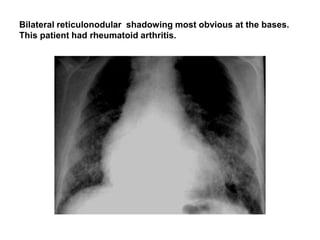

Bilateral reticulonodular shadowing most obvious at the bases.

This patient had rheumatoid arthritis.

reticulonodular pattern

• A combined reticular and nodular pattern, the

reticulonodular pattern is usually the result of the

summation of points of intersection of

innumerable lines, creating the effect on chest

radiographs of superimposed micronodules.

• The dimension of the nodules depends on the

size and number of linear or curvilinear

elements.

Chest radiograph shows reticulonodular pattern